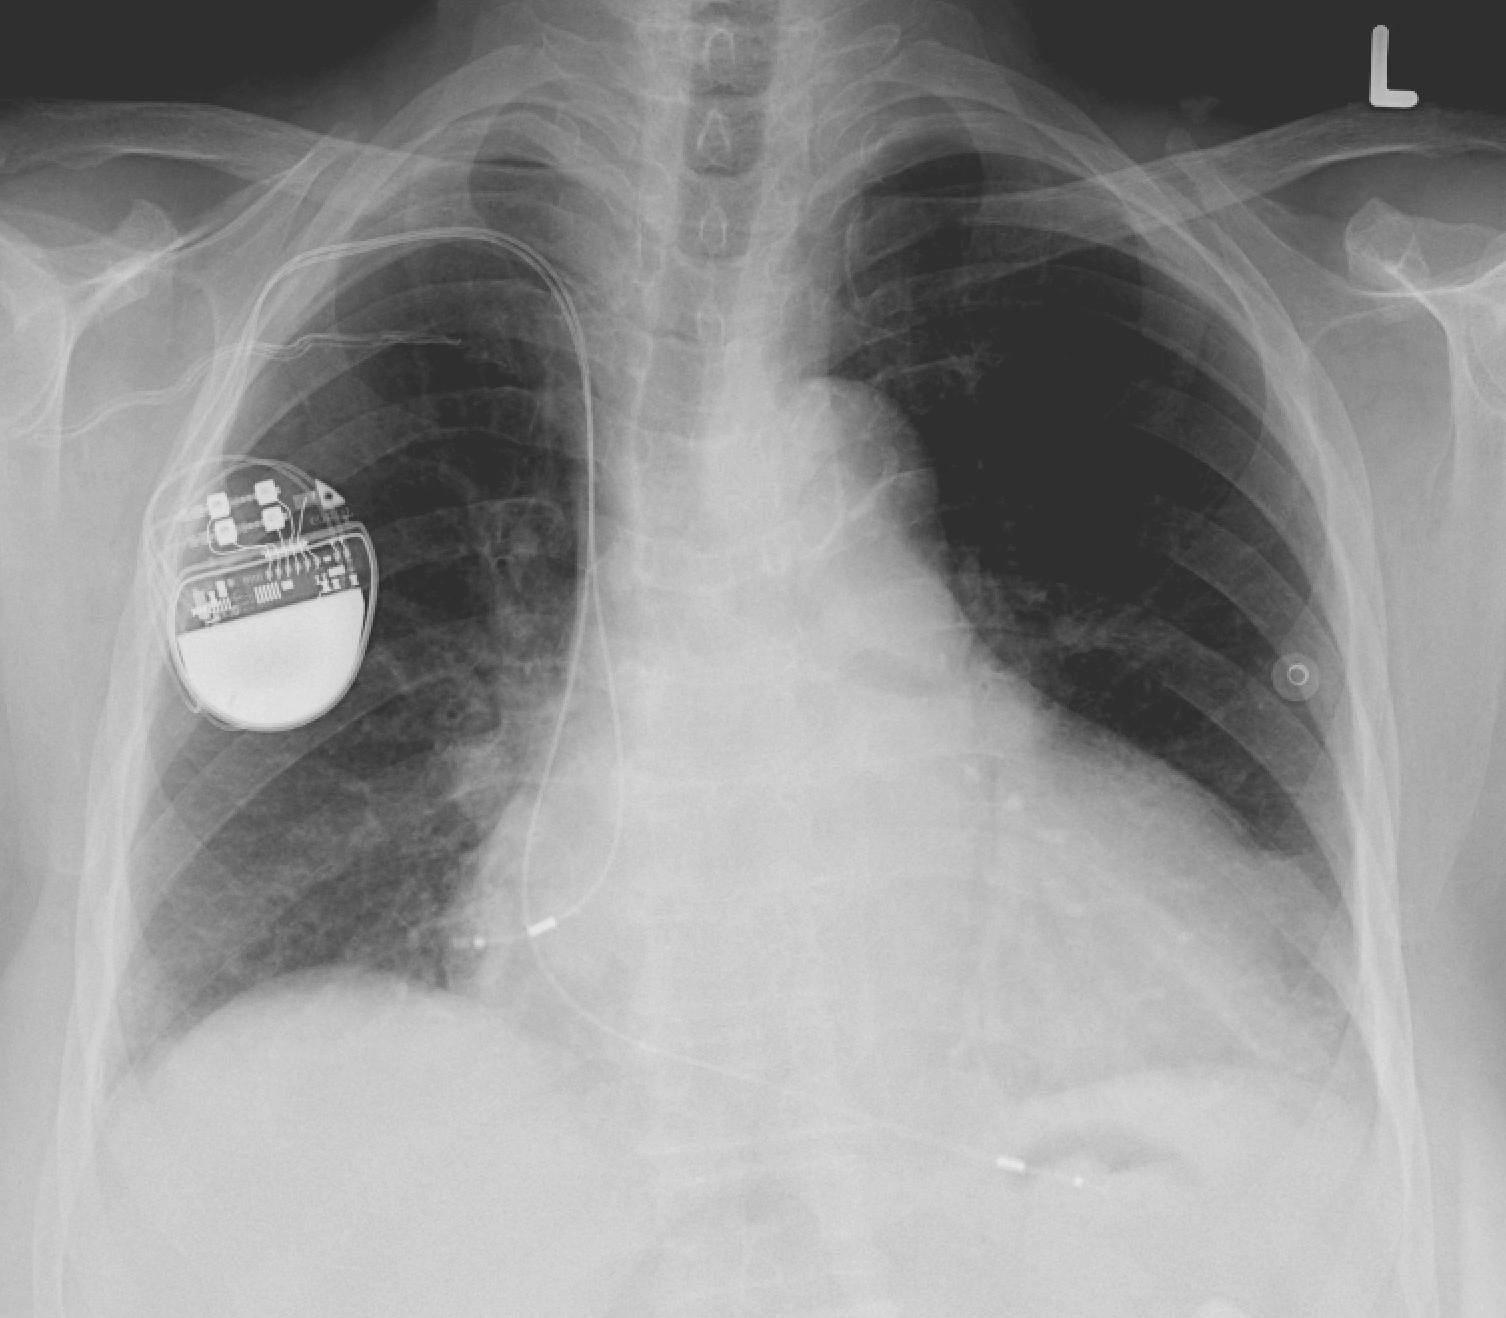

The Food and Drug Administration (FDA) is a United States agency responsible for regulating medical devices among other functions. The regulation process entails a lengthy pre-market process that looks at pre-clinical trials, clinical trials, the warehouse in which the device is manufactured, ethics behind the device, and more. When it comes to the device…